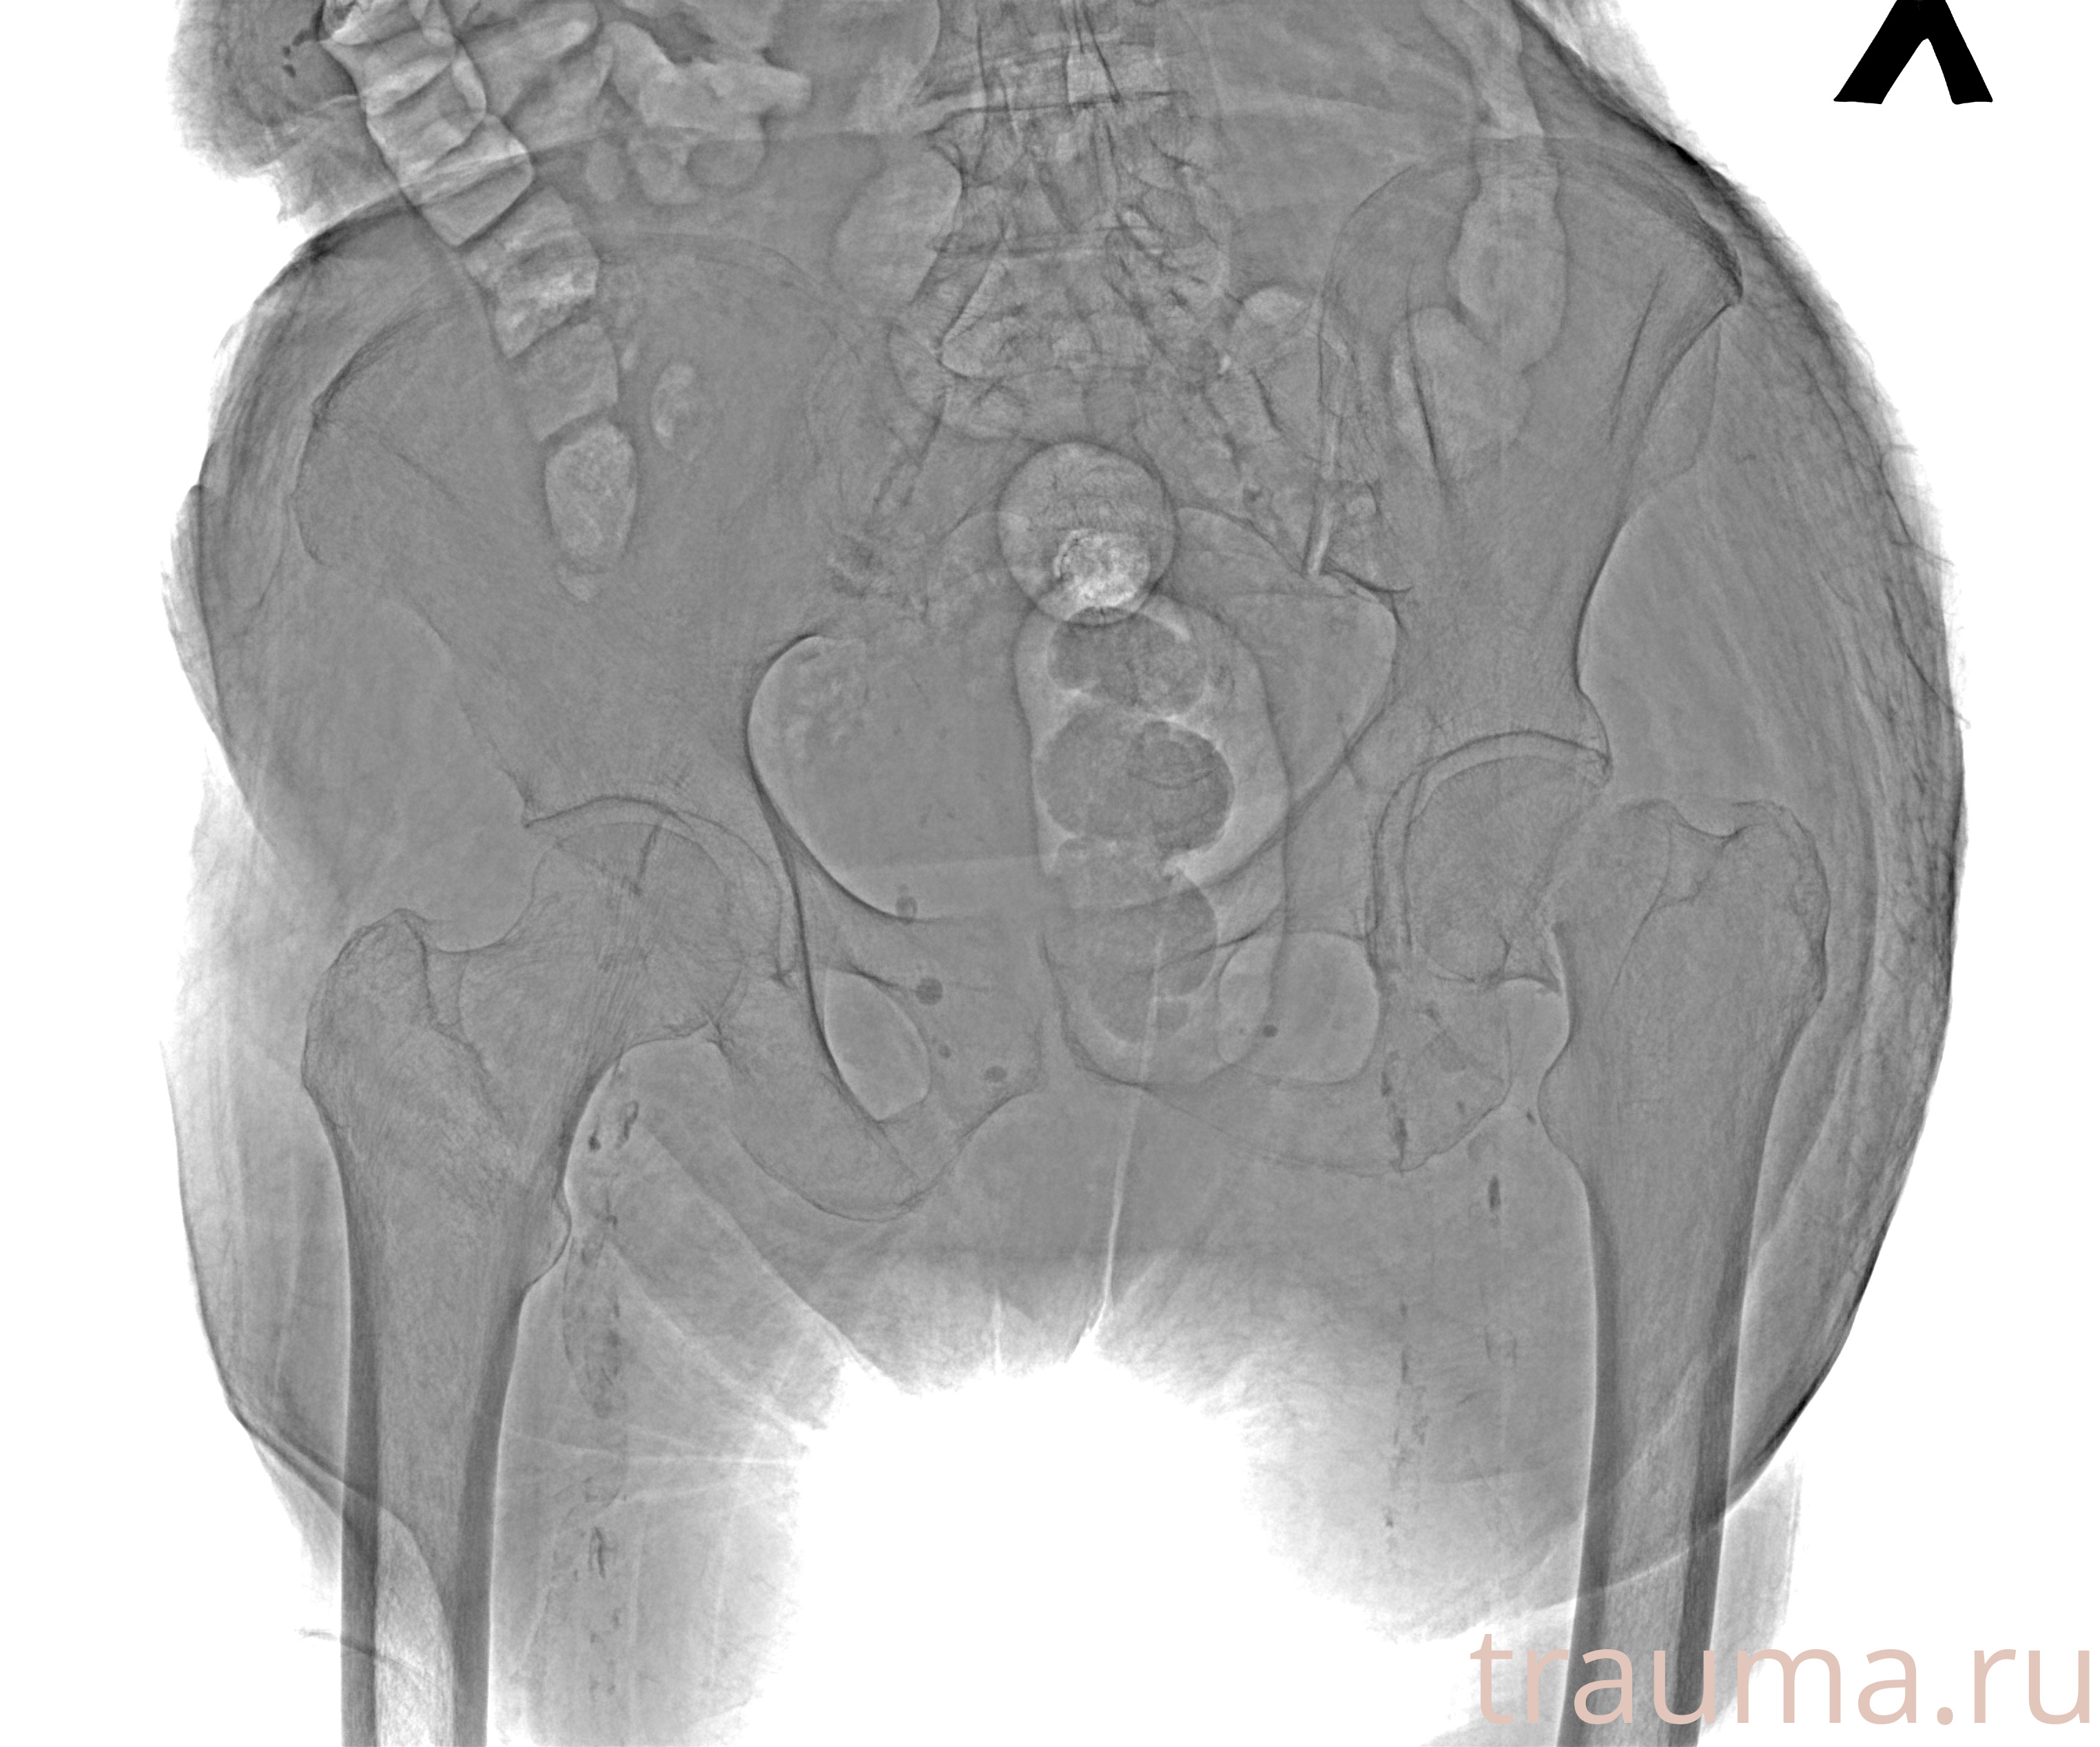

Рентгенограммы

Рентген на дому: по вашему адресу приезжает врач-рентгенолог, травматолог-ортопед с мобильным рентгеновским аппаратом, проводит диагностику травмы или заболевания, делает необходимые рентгенограммы, дает рекомендации по дальнейшему лечению. Получить качественные снимки в домашних условиях возможно благодаря уникальной методике, разработанной МосРентген Центром для института  Склифосовского